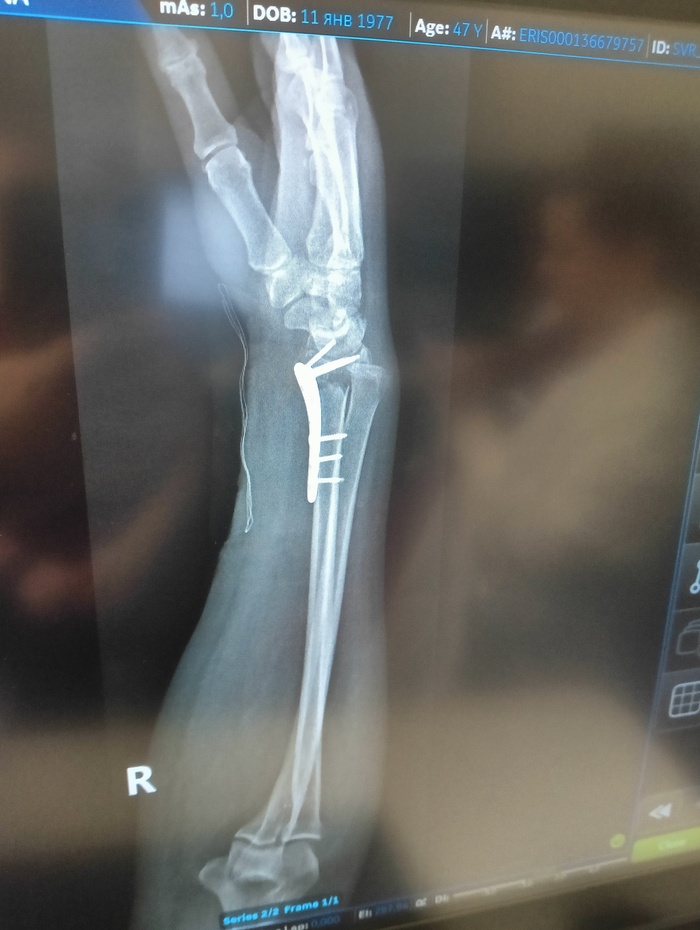

22 июля я неудачно упала и получила оскольчатый перелом дистального метафиза лучевой кости со смещением отломков более чем на 1/2 ширины диафиза. Открытый перелом шиловидного отростка локтевой кости. Была месяц в гипсе, но ничего не срослось. Диастаз костных отломков стал до 4 мм. Локтевая ушла в сторону на 5 мм. На 3 месяц после перелома мне сделали операцию, поставив титановую пластину. Сегодня сделала ренген и получила вот такой результат: Застарелый сомнительно консолидирующийся перелом дистального метафиза правой лучевой кости в условиях накостного МОС. Помимо отрыва шилообразного отростка локтевой кости, видно, имеется разрыв дистального радио-ульнарного сочленения.

верхние ффото через 2 месяца после перелома, потом после операции и 2 нижние - сегодня